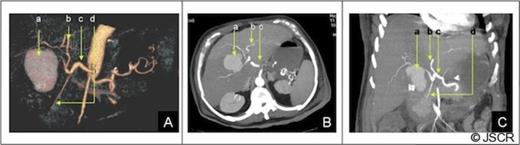

Forty-eight hours after admission the patient had an episode of haemodynamic instability suggestive of septic shock, which was also associated with a drop of 15 points in haematocrit levels (haematocrit: 24, WBC: 33 000). Empirical antibiotic therapy was begun and abdominal contrast-enhanced computed tomography (CT) was performed. CT showed a pseudoaneurysm of the right hepatic artery (RHA) of 7 cm in diameter, haemoperitoneum, intrahepatic dilatation of the biliary tree bile duct and the presence of hepatic infarction, and duodenal wall involvement (Figures 1 and 2).

CT of the abdomen: A) Tridimensional reconstruction, B) Axial slice C) Coronal slice (a;.Pseudoaneurysm of the right anterior hepatic artery, b;Left hepatic artery, c;Common hepatic artery, d;Gastroduodenal artery). The right posterior hepatic artery arises from the left hepatic artery.